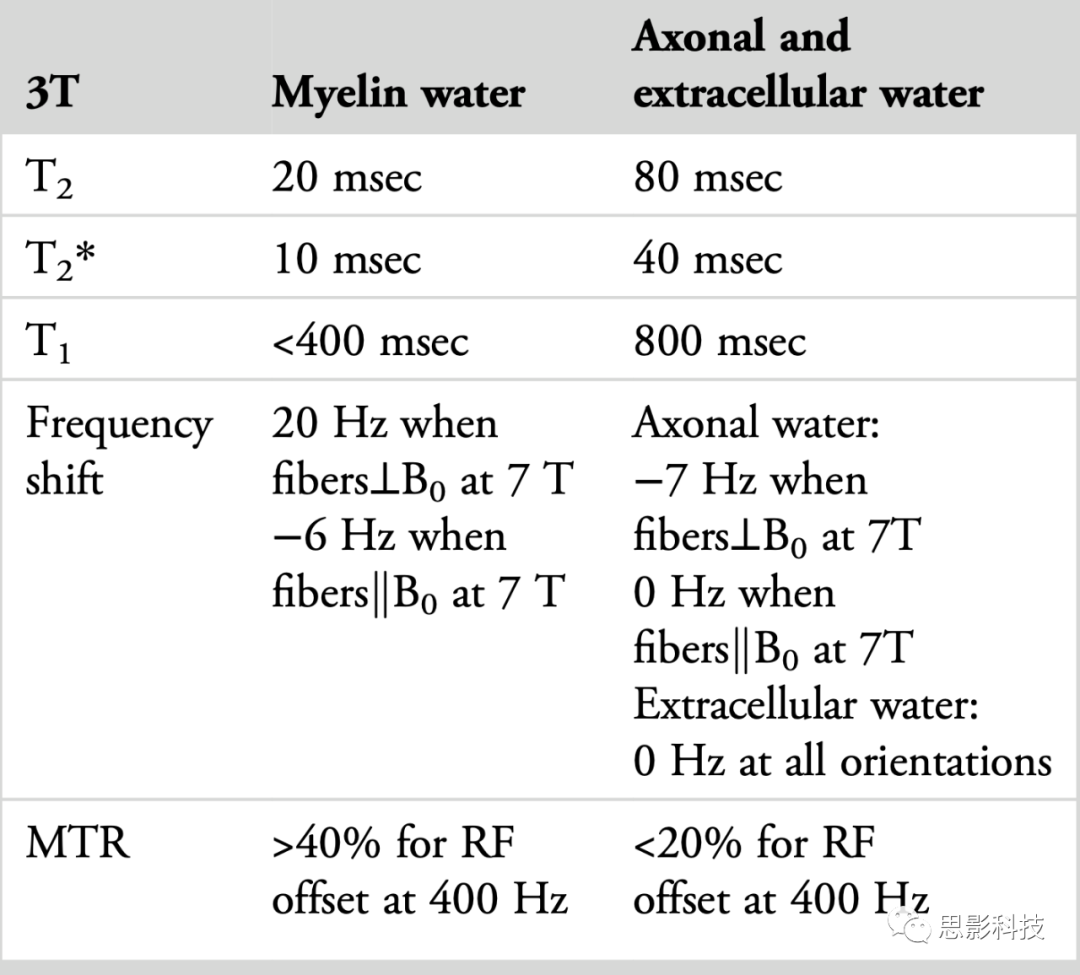

横向弛豫:与髓鞘的强烈相互作用使髓鞘水的T2在3T时缩短到大约20毫秒。5这个T2的范围可以在常规MWI序列中检测到,并且明显短于AEW信号。因此,当测量T2弛豫时,它显示为双(或多)指数衰减,如图2a所示。与T2相似,髓鞘水的T2*也比AEW的短。髓鞘水的较短T2*来源于髓鞘水的短T2和髓鞘的磁化率效应(图2d-i;参见下面的共振频率移位以获取更多细节)。

纵向弛豫:已报道髓鞘水的T1弛豫时间比AEW的短(图2b 23)。与T2相似,髓鞘水与周围脂质的相互作用引起交叉弛豫,导致髓鞘水的纵向弛豫时间减少。然而,实验中测得的T1值取决于采集参数(例如,反转脉冲类型和重复时间[TR]),这是由于反转效率和隔室水交换的效果。尽管存在这种复杂性,人们可以利用这一特性选择性地获取髓鞘水信号(参见基于T1的MWI)。

共振频率移位:这是髓鞘水信号与AEW信号不同的较少为人知的特性。关于髓鞘的磁化率的最近研究表明,髓鞘水的共振频率取决于白质纤维与B0之间的相对方向(图2d-i 15, 27)。当白质纤维垂直于B0时,髓鞘水频率移位显示出大的正频率移位,而轴突水产生相反的频率移位。这一独特特性的起源被归因于髓鞘水的磁化率各向异性。这种频率移位已被用于基于T2*的MWI以改进髓鞘水成像。

磁化转移:MT,起源于水分子池和大分子之间的磁化交换,是一个众所周知的现象。MT的效应大小(即,MT比率或MTR)受到大分子(例如,髓鞘)浓度的影响。已经证明髓鞘水信号的MT效应比AEW信号的高2-3倍(图2c 15, 16)。

表1:髓鞘水信号与AEW信号的特性对比

髓鞘水信号与AEW(轴突/细胞外水)信号显示出不同的特性。其中一些属性被用来生成髓鞘水图像。除非另有说明,否则所有值都是在3T下的近似值。